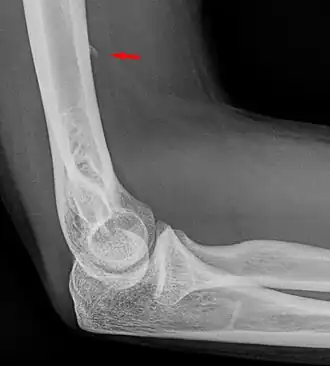

Larger supracondylar process seen on a lateral radiograph of the elbow

The supracondylar process of the humerus (also known as an avian spur) is a variant bony projection on the anteromedial aspect of the upper arm bone (humerus), about 5–6 cm above the medial epicondyle.[1] It is directed downward, forward and medially pointing to the medial epicondyle. A fibrous band, Struthers ligament, may connect this process to the medial epicondyle.[2] This variation has a prevalence of 0.68% and is significantly more common in women than in men.[3]